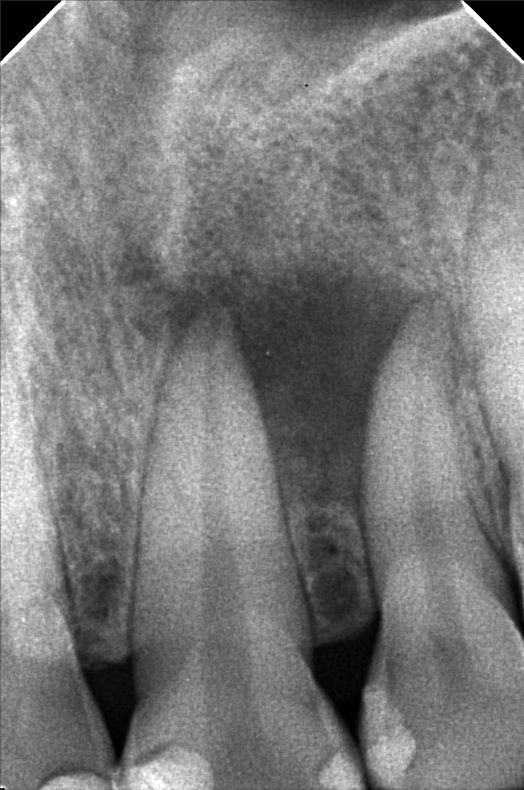

Edit Record Check our patient data records. Add patient information Patient Info Profile picture Last Name First Name Middle Name Birthdate Age Street Barangay City Country Zip Code Contact number Email Procedure 06/06/25 #11,21,22 w/ abcess PA9 abcess) w/ xray Recommendation: RCT or RCT w/ apecoectomy and retrograde filling File atecotech2i886_f_7.bmp File 2 atecotech2i6be6_f.bmp File 3 File 4 File 5 File 6 File 7 File 8 File 9 File 10 File 11 File 12 File 13 File 14 File 15 File 16 File 17 File 18 File 19 File 20 Retain Record Retain Record Yes No Save Your Changes